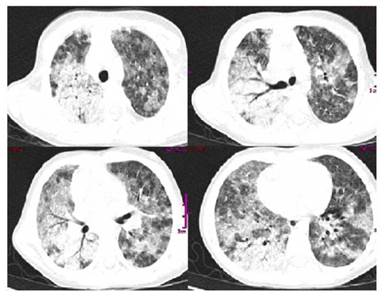

A new chest X-ray showed progression of the opacities, so were performed blood cultures and nasopharyngeal swab for the detection by immunofluorescence of respiratory syncytial virus and influenza A and B viruses, whose results were negative. A computed tomography of the thorax was requested, showing generalized ground-glass lesions with parenchymal consolidation of multifocal pulmonary appearance, suggestive of alveolar hemorrhage associated with a possible infectious process (Figure 1).

Chest radiography may show diffuse alveolar opacities of alveolar occupation and acute onset. Chest tomography may show nonspecific findings; however, it is common to see different degrees of frosted glass pattern occupying much of the lung fields. Histopathology is characterized by intralveolar red blood cells and fibrin, with accumulation of hemosiderin within the macrophages (siderophagia) 4-6.